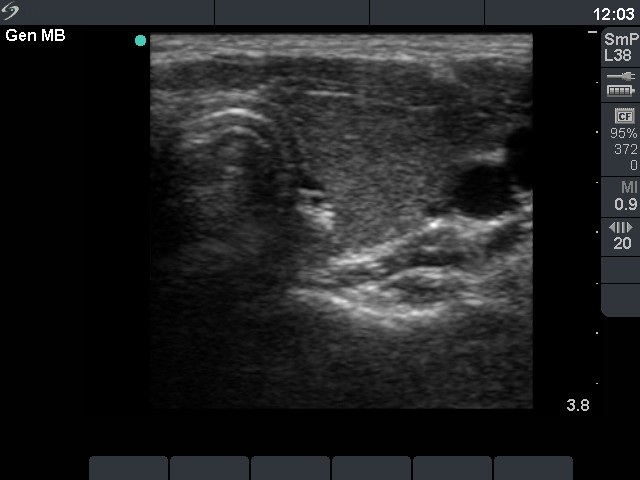

Follow-up investigation 12 months after first visit (ultrasonographic picture 4)

Patient on daily 10 mg methimazole therapy in euthyroid state

Left lobe, transverse scan. The thyroid is moderately hypoechogenic.